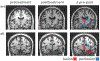

Methods: This prospective trial randomized patients with unilateral hippocampal sclerosis and concordant video-EEG findings to SRS versus ATL. Humphries perimetry was obtained at 24 m after surgery. VFD ratios (VFDR = proportion of missing homonymous hemifield with 0 = no VFD, 0.5 = complete superior quadrantanopsia) quantified VFD. Regressions of VFDR were evaluated against treatment arm and covariates. MRI evaluated effects of volume changes on VFDR. The relationships of VFDR with seizure remission and driving status 3 years after surgery were evaluated.

Results: No patients reported visual changes or had abnormal bedside examinations, but 49 of 54 (91%) of patients experienced VFD on formal perimetry. Neither incidence nor severity of VFDR differed significantly by treatment arm. VFDR severity was not associated with seizure remission or driving status.

Conclusion: The nature of VFD was consistent with lesions of the optic radiations. Effective surgery (defined by seizure remission) of the mesial temporal lobe results in about a 90% incidence of typical VFD regardless of method.